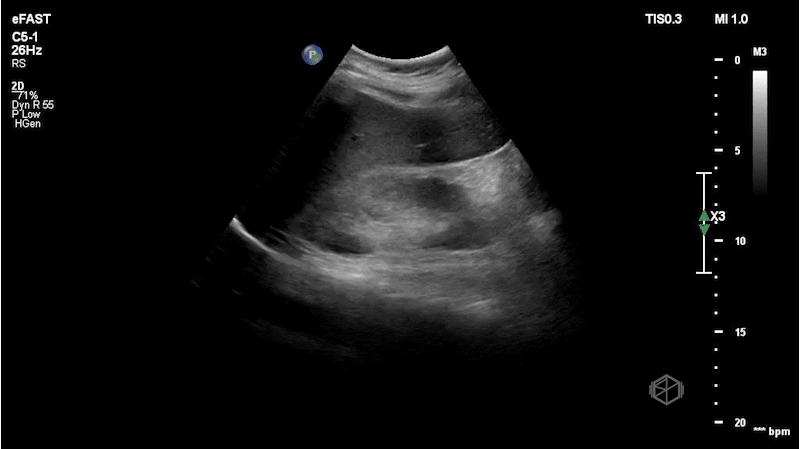

The next SonoProp goes to Dr. Obioma Nkemakolam.

He was evaluating a 54-year-old male with a history of hypertension, hyperlipidemia, coronary artery disease, and current everyday smoking, who presented with shortness of breath. The patient was significantly hyperglycemic and was thought to be in DKA. He was also borderline hypotensive and there was a lacy appearance to his abdomen. The patient had a stat abdominal aorta scan that demonstrated the following:

There is a large circular anechoic structure in the middle of the scan. If you thought this was the abdominal aortic aneurysm — surprise — it’s not.

This a distended fluid filled stomach, a common false positive for FAST/FAFF examinations as well as aorta exams.

Patient had a CTA that demonstrated a normal aorta as well as diffuse gaseous distention of the esophagus mild/moderate gastric distention with fluid and gas due to recent alimentation.

Diagnosis: Distended stomach filled with liquid/food

• The aorta has some key landmarks that should be identified before determining the structure is the aorta on ultrasound - the vertebral body should be right behind it. The IVC should be next to it on the left. The spinal body should be visualized. The aorta is also pulsatile and will have the celiac trunk (if the proximal aorta can be visualized) and superior mesenteric artery visible.

• This structure seems to be coming from the left upper quadrant, with no vertebral body behind it and no IVC next to it. The color doppler signal is unreliable due to the patient’s heavy breathing.

• The stomach will appear as a cystic organ when distended with fluid. If there is clear fluid there may be echogenic gas bubbles visible (28191199). There many hints that the object in Dr. Nkemakolam’s case is the stomach and not the aorta.

• Breathing and peristalsis of the stomach may cause doppler noise.